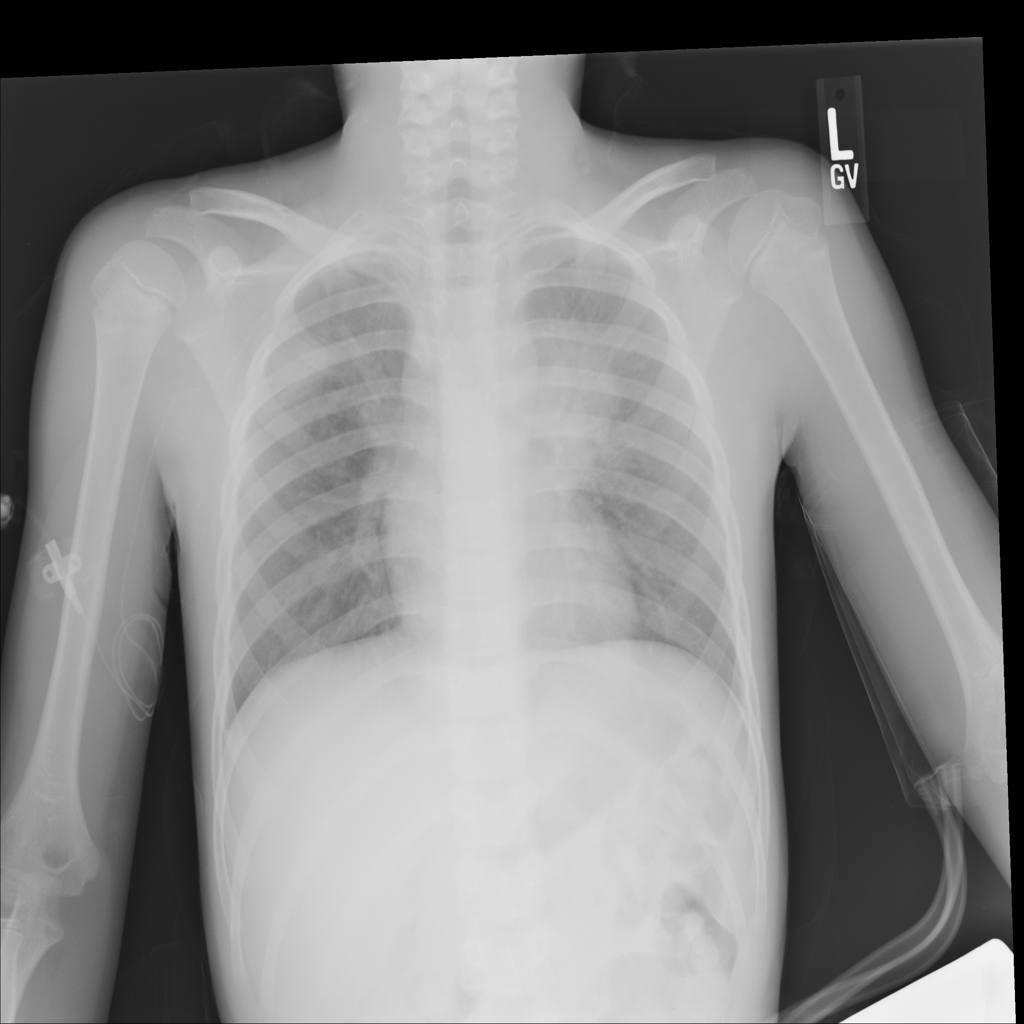

Mass

A mass is a larger focal opacity or lesion seen on the image. It is a descriptive finding that can have several causes and usually needs more imaging or clinical context to characterize.

PAT-50E5 · IMG-008Mass

PAT-50E5 · IMG-008

PA